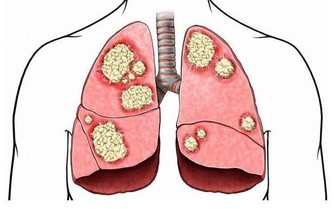

5.三高問題

預防“三高”,晚餐當僅七成飽,當有“飽感”則證明飲食已過量,對消化器官和腎臟器官會產生負擔。